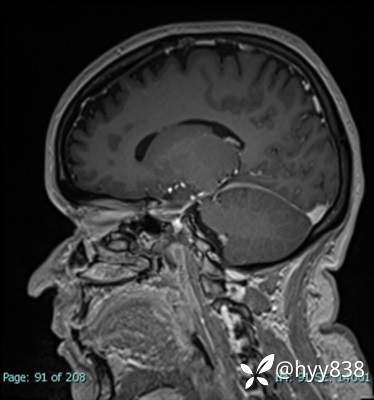

MRI sag T1WI + axi T2WI+FLAIR